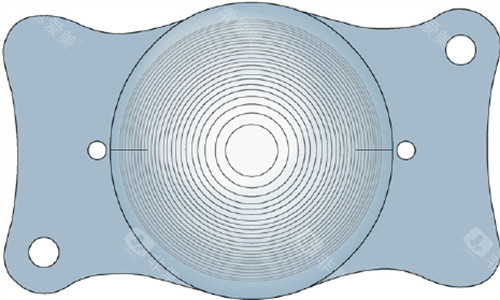

1. 动态光学设计,适配复杂眼况

德国人类光学创新“可变光学区”技术,以MCX11ASP型号为例,其光学直径可在4.5-6.0毫米间动态调节。

这一设计突破了传统晶体固定光学区的限制,尤其适合高度近视、远视及合并眼底病变患者。

例如,高度近视患者因眼轴较长,常伴随视网膜变薄,动态光学区可减少对眼底的压力,降低术后并发症风险。

2. MCX11ASP:可变光学区技术标杆

技术亮点:光学直径动态调节范围达4.5-6.0毫米,可适配不同瞳孔大小及眼底条件。

适用人群:高度近视、远视及合并视网膜病变患者,如糖尿病视网膜病变术后矫正。

价格区间:单眼价格约12000-15000元,定位中高端市场。